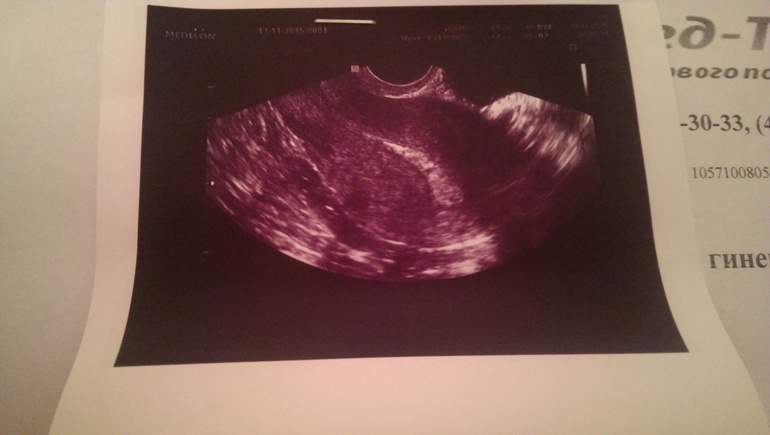

День Х наступил!Вобщем я приехала) на Узи нашли2мм штучку в матке) полость матки 9, 5 мм жт в правом яичнике) она не уверенна, говорит, что может назвать беременностью образование от 5 мм , я в странных чувствах, оно не оно! Через10 дней сказала еще прийти

У меня такая же фотка с узи,диагноз эндометрит-воспаление матки...дай Бог,чтоб у вас была Б,а не эта бяка...